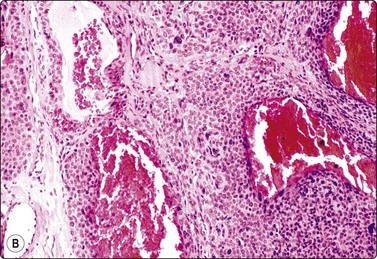

Dermatofibrosarcoma protuberans (DFSP) (Fig. 14.30)

The cytological findings in DFSP have been reported by Domanski and Gustafson.74 The yield is abundant of both tissue fragments of variably cohesive spindle cells and dispersed single cells and stripped nuclei. There is moderate anisokaryosis, but the nuclear chromatin is granular and nucleoli are small. A streaming arrangement that vaguely suggests a storiform pattern may be seen. The tumor cells stain positively for vimentin and CD34. The main differential diagnoses are low-grade fibrosarcoma and monophasic fibrosarcoma-like synovial sarcoma. The clinical presentation is an important clue to diagnosis

image image image

Fig. 14.30 Dermatofibrosarcoma protuberans (DFSP)

(A) Dispersed single cells and stripped nuclei with moderate anisokaryosis, but granular nuclear chromatin (MGG, MP); (B) A streaming arrangement that vaguely suggests a storiform pattern may be seen (MGG, MP); (C) The tumor cells stain positively for CD34 (cell block preparation, CD34).